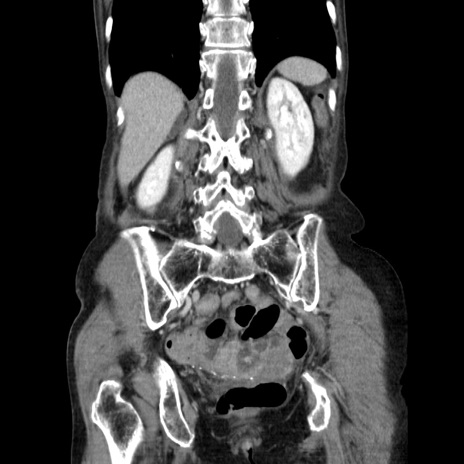

症例25(冠状断像)

【症例】80歳代女性

【主訴】胸のつかえ感

【現病歴】約9時間前に食後から胸のつかえた感じあり、嘔吐あり、来院。

【既往歴】胃癌(全摘)、胆摘、虫垂炎

【身体所見】心窩部に圧痛あり、反跳痛なし。

【データ】WBC 5700、CRP 0.05